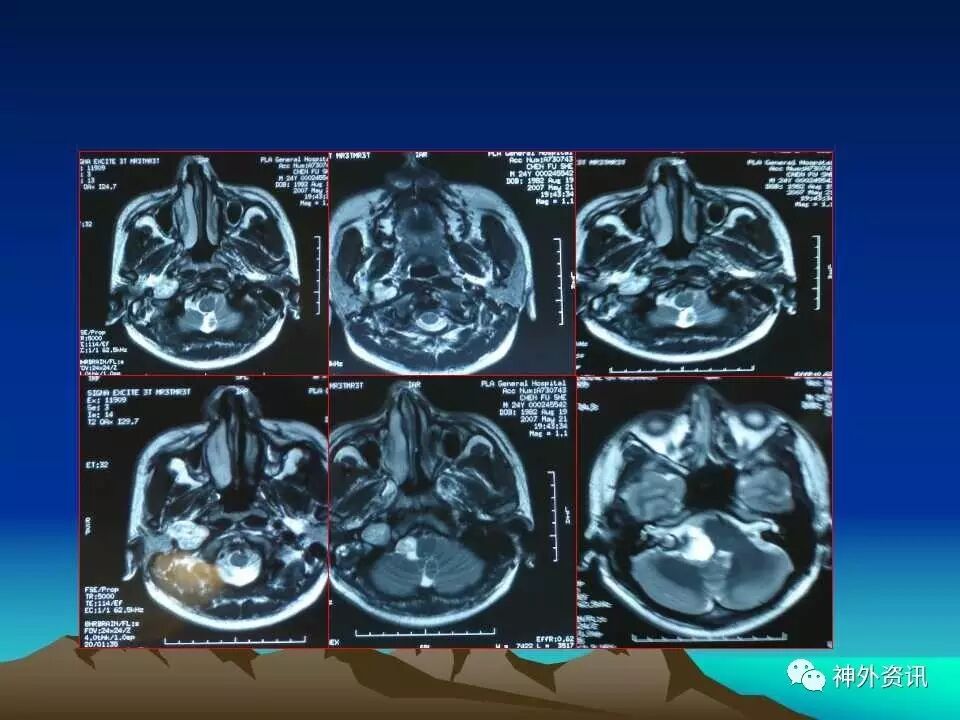

“枕下极外侧髁上入路处理颈静脉孔区肿瘤:

75例分析和总结”精彩讲课视频